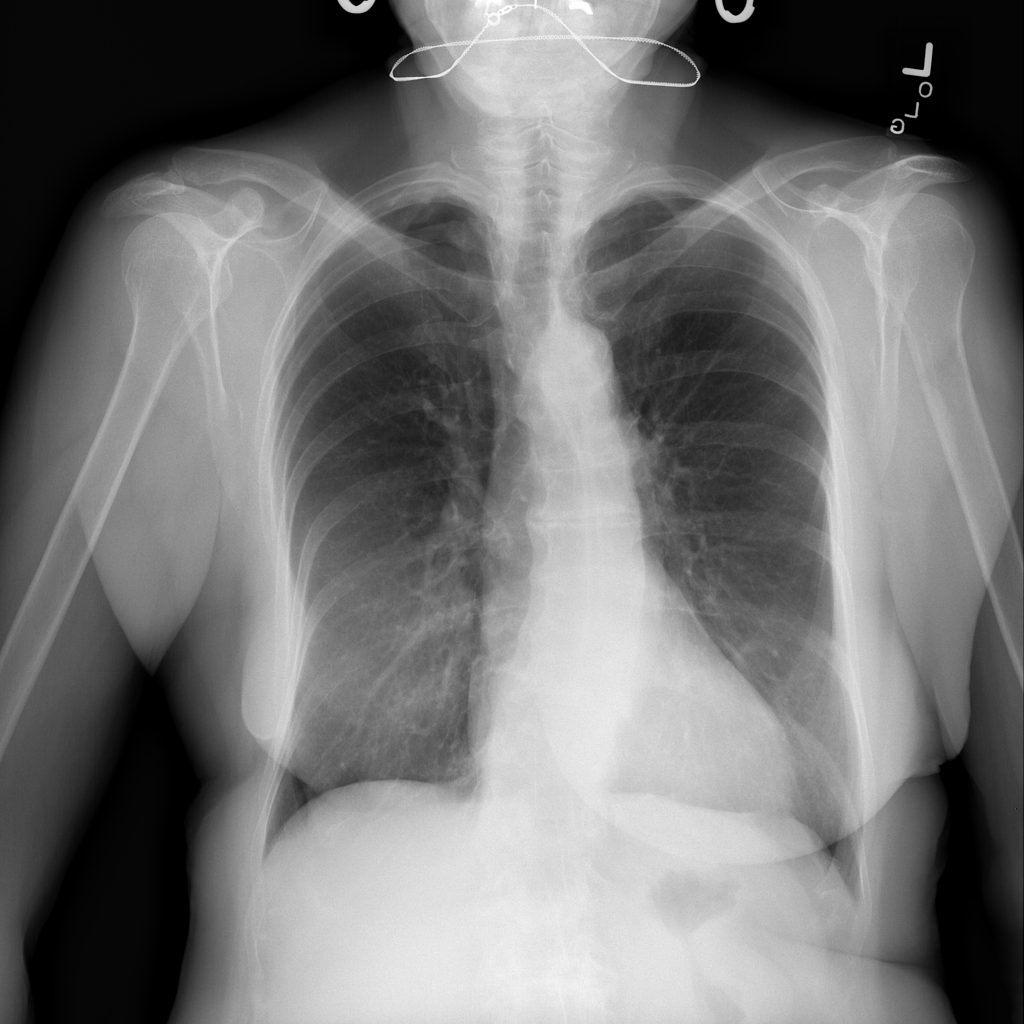

Nodule

A nodule is a small rounded opacity in the lung or chest field. It is a descriptive imaging finding that can be benign or more concerning depending on size, appearance, and context.

Showing up to 90 reference images for Nodule.

PAT-250B · IMG-000Nodule

PAT-250B · IMG-000

PA